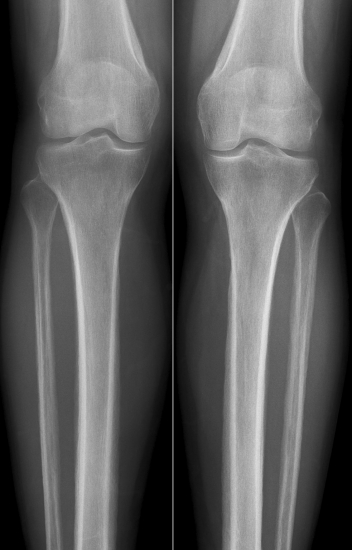

Der Kurs diente explizit zur Vorbereitung für das schriftliche Examen. Hierzu besprachen die Referenten viele verschiedene Multiple-Choice-Fragen mit radiologischem Bildmaterial. Abgedeckt wurden Themengebiete wie z. B. Thorax, Neuroradiologie, Angiographie, Urogenitaltrakt und mehr. Passend zur entsprechenden Röntgen-, CT- oder MRT-Aufnahme erklärten die Radiologen, welche Informationen sich aus den bildgebenden Modalitäten gewinnen lassen und natürlich auch, auf welchem Weg man die Examensfrage lösen kann.

Häufig zeigten die Referenten, wie sich falsche Antwortmöglichkeiten allein mit logischem Denken ausschließen lassen. Eine Jejunalstenose könne beispielsweise in einem Röntgenbild nicht vorliegen, wenn der Colon luftgefüllt ist.